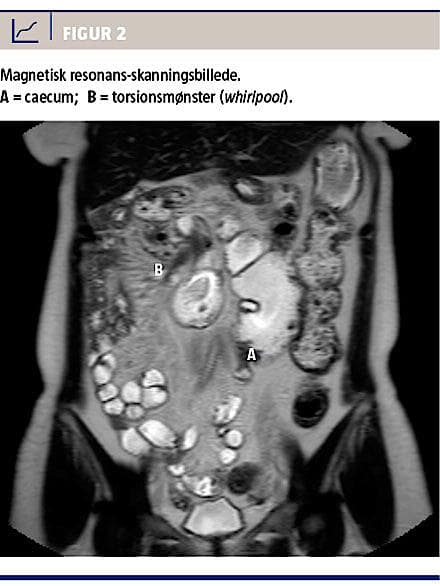

En ultralydskanning af øvre abdomen viste normale forhold. På baggrund af en colonindhældning foretaget 13 år tidligere blev der rejst mistanke om malrotation. Efterfølgende MR-skanning og computertomografi (CT) viste malroteret colon med caecum placeret til venstre for midtlinjen i umbilikalniveau. Skanningen viste desuden torsionsmønster i tyndtarmskrøset beliggende i højre øvre kvadrant, vægfortykkelse af duodenum og inflammation i krøset i det torkverede område (Figur 2). Patienten blev efterfølgende indkaldt til laparoskopisk deling af de laddske bånd, hvor man verificerede diagnosen. Der blev foretaget deling af et langstrakt fladt bånd mellem colon ascendens/caecum og duodenum/lever/laterale bugvæg samt detorkvering af mesenteriet. Operationen forløb planmæssigt med et ukompliceret postoperativt forløb.